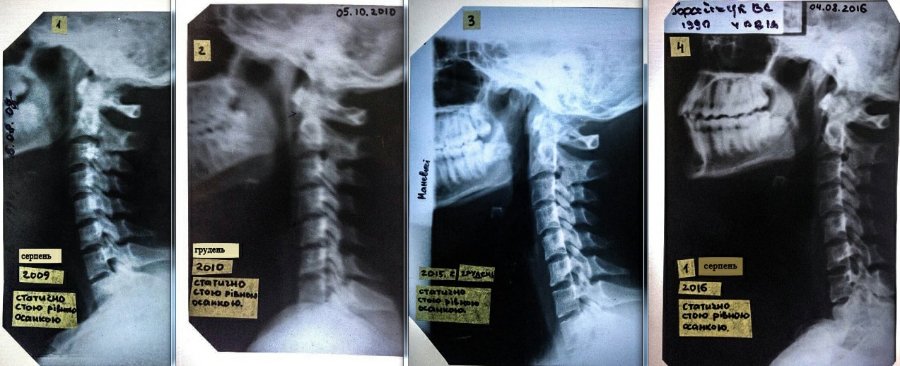

Лучанка Валентина Горайчук потребує допомоги. Дівчина збирає кошти, аби поїхати на діагностику до Києва. Бо у Луцьку, за її словами, лікарі допомогти їй не можуть.

Без корсета шия не тримається! А в ньому стає нестерпно.

В мене є попередній діагноз професора вертебролога зі Львову, пов'язаний з динамічною патологією. М'язи шиї не слухаються. Хвороба не христоматійна, випадок мабуть одиничний. Я в розпачі. Пишіть, якщо хтось щось про таке чув або знає! Луцькі лікарі розводять руками, або не допомагають і діагноз не підтверджують. Всі, хто мене знає, дуже багато людей - можуть підтвердити, що я НЕ видумую і проблеми були ще в школі, в інституті рік не могла ходити, я лежала в лікарнях неодноразово», - пише дівчина.

«Мені стає гірше! Хвороба прогресує. Не знаю чому, і спинити важко, якщо симптоми посилюються. Я терплю і збираю силу волі в кулак, в надії, що доїду до Києва і мені пощастить з лікарем або командою. Я за все життя тільки і навчилась, що терпіти, чекати і любити життя.

Яшан Василь Петрович - с. Боголюби, відділення профпатології і вертебрології Волинської обласної клінічної лікарні. Не пробували звернутися? Лікар - "Касьян" Волинської області. До нього їдуть з усієї України. А заключення Маневицької ЦРЛ і знімки - це ще не підстава збирати кошти на діагностику в Київі.